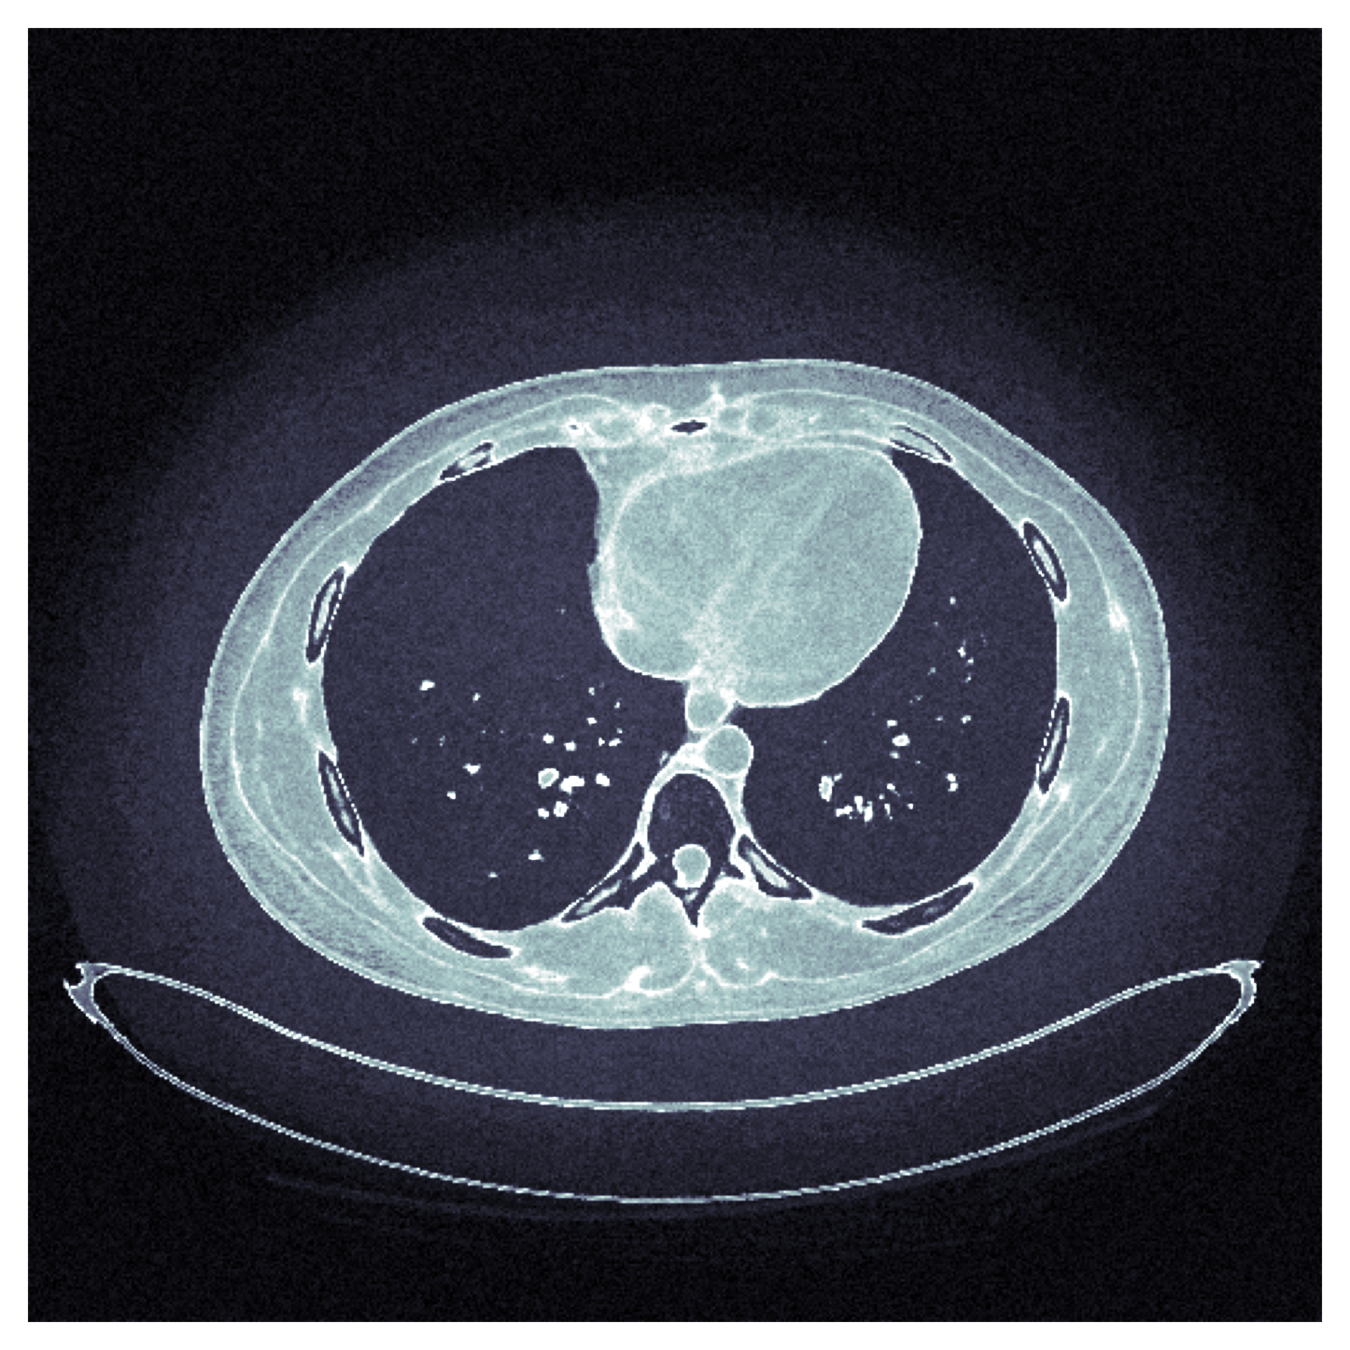

Uncertainty Quantification

How to quantify and report uncertainty?

Filtered Back Projection

Diffusion Model

For an observation \(y\)

\[y = x + \epsilon,~\epsilon \sim \mathcal{N}(0, \sigma^2\mathbb{I})\]

reconstruct \(x\) with

\[\hat{x} = F(y) \sim \mathcal{Q}_y \approx p(x \mid y)\]

Teneggi, J., Tivnan, M., Stayman, W., & Sulam, J. (2023, July). How to trust your diffusion model: A convex optimization approach to conformal risk control. In International Conference on Machine Learning. PMLR.